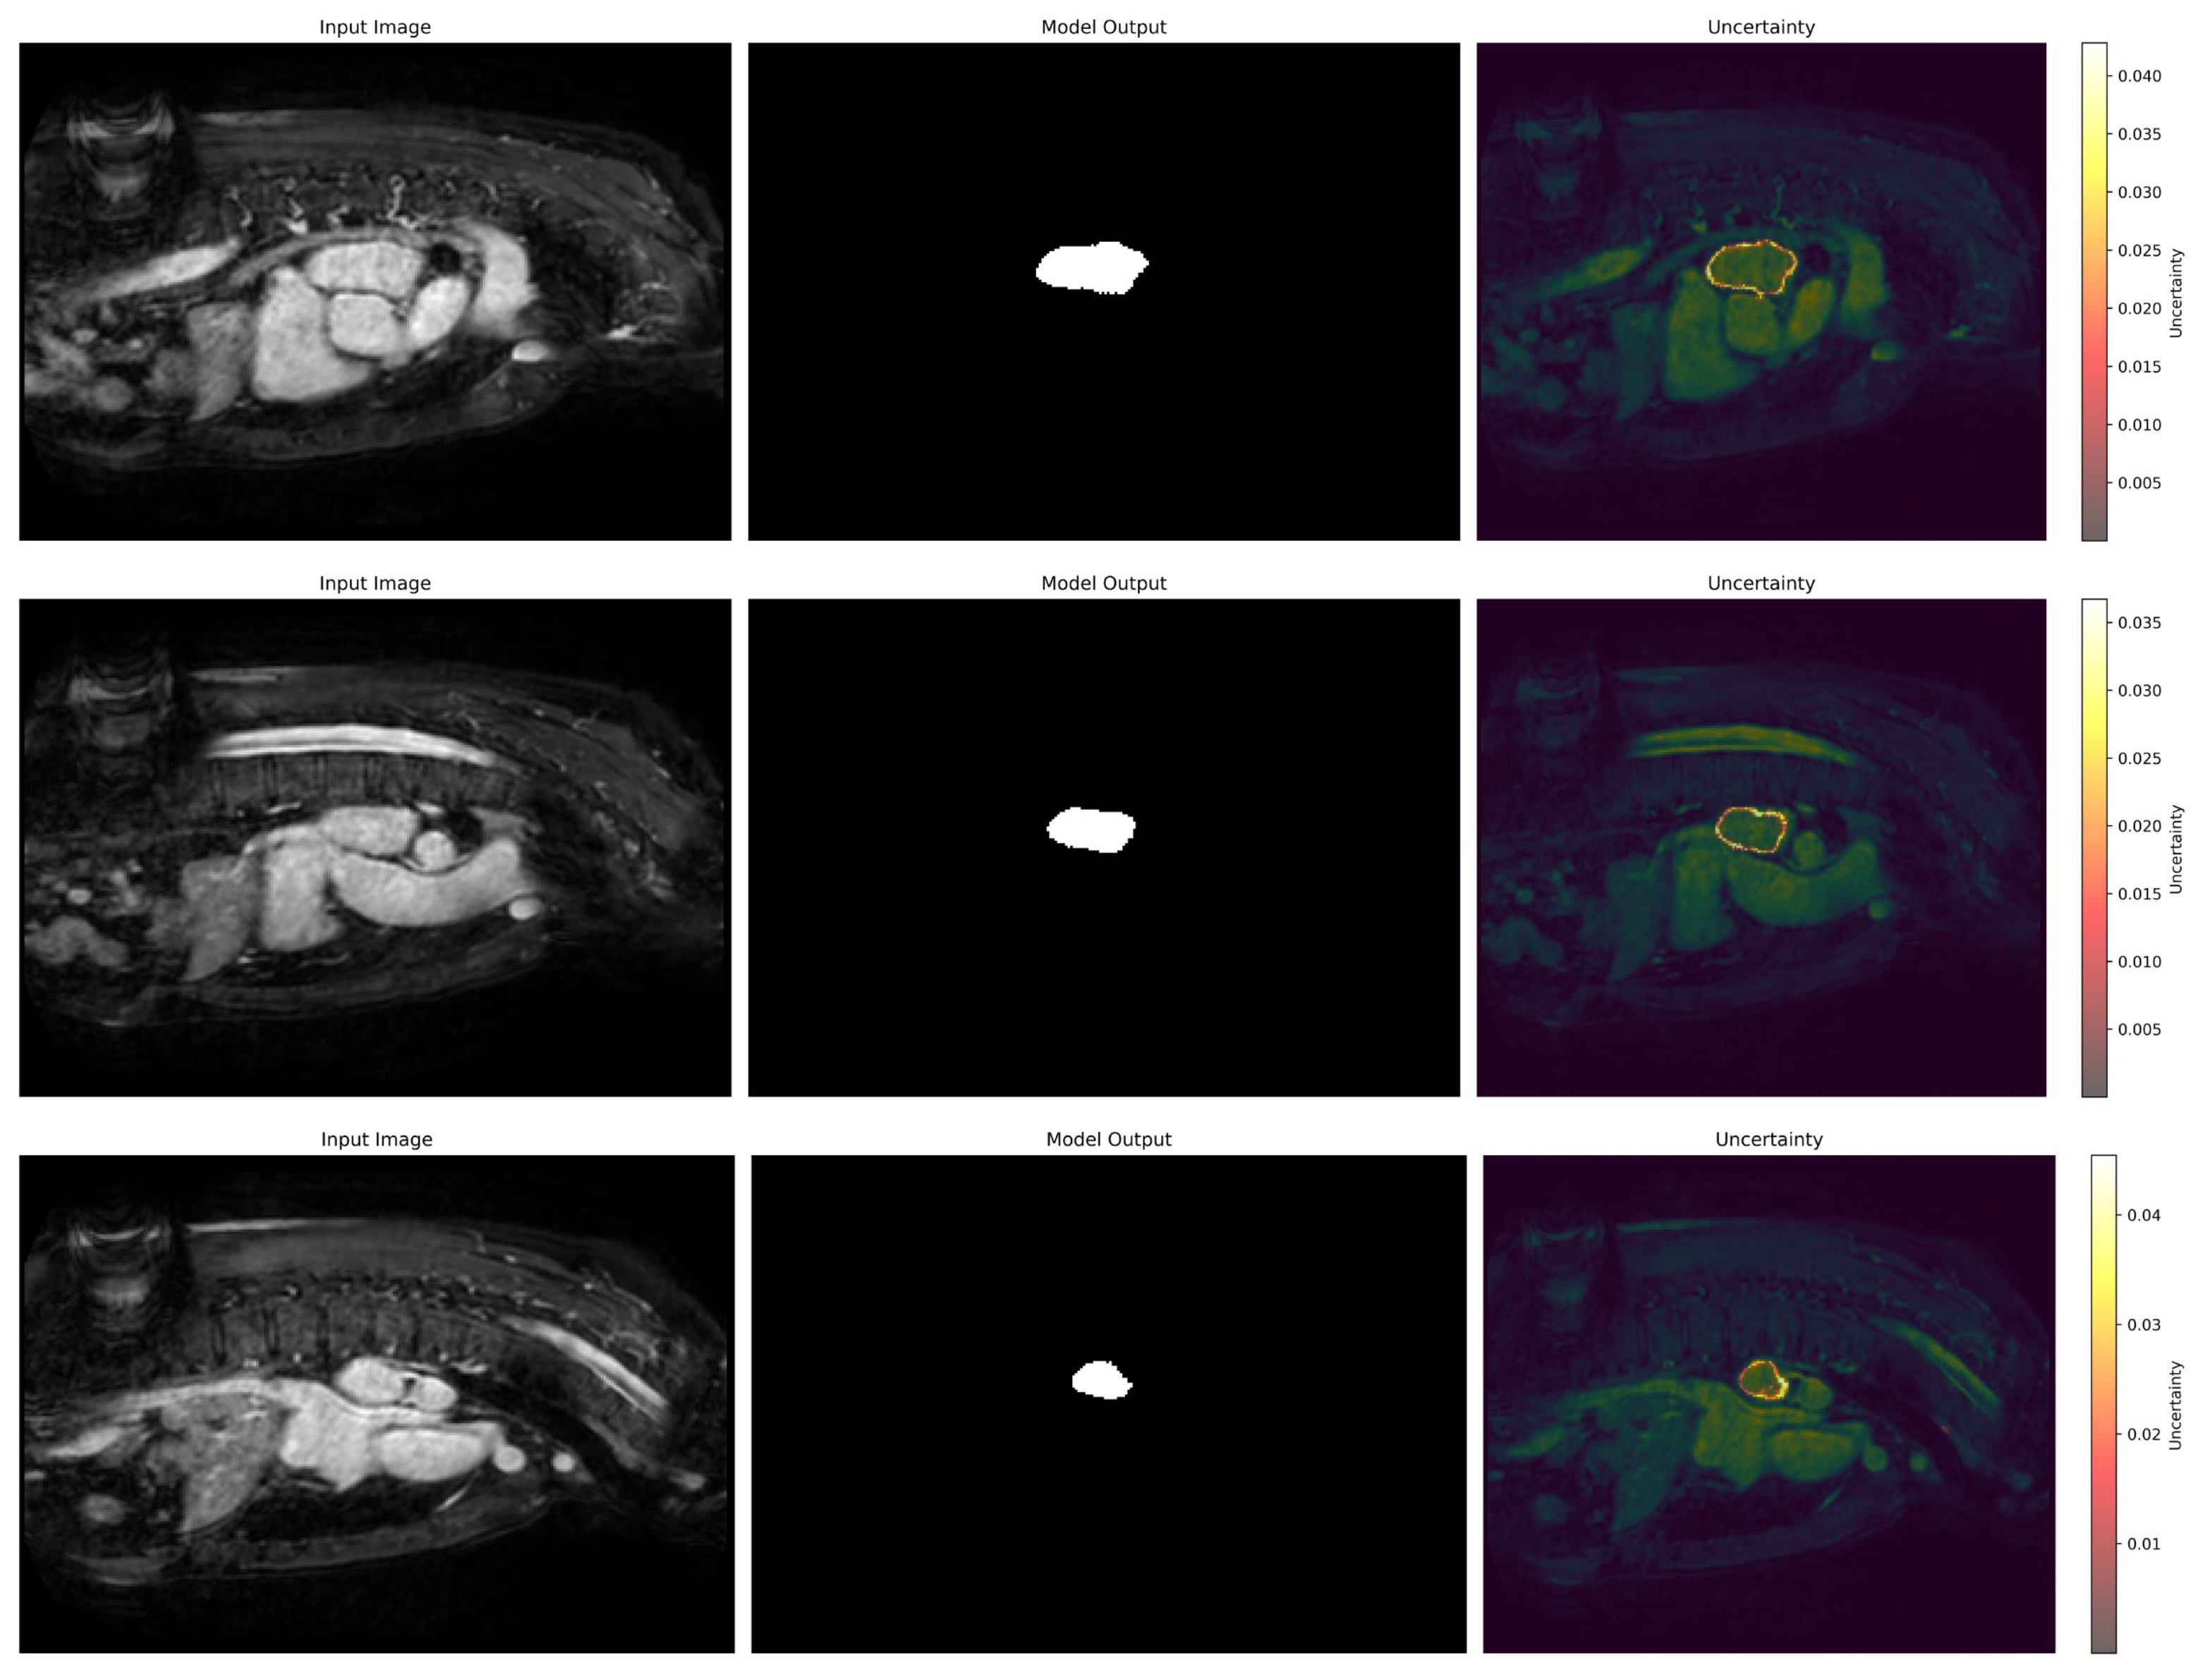

3.6. Uncertainty Estimation